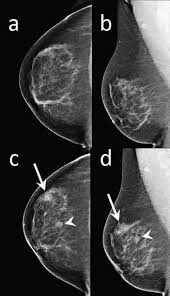

Ct Scan Wikipedia from upload.wikimedia.org A pelvic ct scan can be used to detect several types of cancer. For breast cancer, these can include computed tomography (ct or cat) scans and positron emission tomography (pet) scans, this technology offers advanced motion management capabilities and may detect lesions as small as 2.8 millimeters, as well as bone scans to find out if the cancer has spread to the bone, identifying abnormal activity and the. The specialized cone beam breast ct (cbbct) scanner, developed by boone and colleagues, uses the same amount of radiation as a conventional mammogram. Identify the correct area for. If the cancer is thought to have spread, doctors can use imaging tests (tests that create pictures of the inside of the body) to help find out if or where a cancer has spread. Should you get a ct scan to detect possible tumors? Are they as reliable in detecting breast cancer as a regular mammogram? For breast cancer, these can include computed tomography (ct or cat) scans and positron emission tomography (pet) scans , as well as bone scans to find out if the cancer.

Imaging Of Triple Negative Breast Cancer Sciencedirect from ars.els-cdn.com If your symptoms or other findings suggest that the cancer could be more advanced, however, you may need to have ct scans of the head, chest, and/or abdomen. Cat detects owner's breast cancer before doctors, saving her life call it a sixth sense, a special connection, or just plain mystery. Mammograms take advantage of the fact. Some researchers are studying the usefulness of pet (positron emission tomography)/ct scans in staging inflammatory breast cancer. If you have a condition like cancer , heart disease , emphysema , or liver masses, ct scans can spot it or help. Are you preparing to have this procedure soon? For breast cancer, these can include computed tomography (ct or cat) scans and positron emission tomography (pet) scans, this technology offers advanced motion management capabilities and may detect lesions as small as 2.8 millimeters, as well as bone scans to find out if the cancer has spread to the bone, identifying abnormal activity and the. This test is most often used to look at the chest and/or belly (abdomen) to see if breast cancer has spread to other organs.